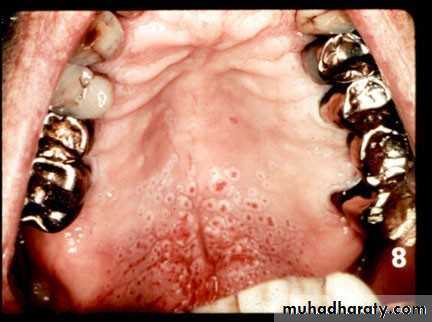

• Denture induced stomatitis

• Upper denture• Due to well fitting denture cutting the washing effect of saliva

• Painless red area• Angular stomatitis